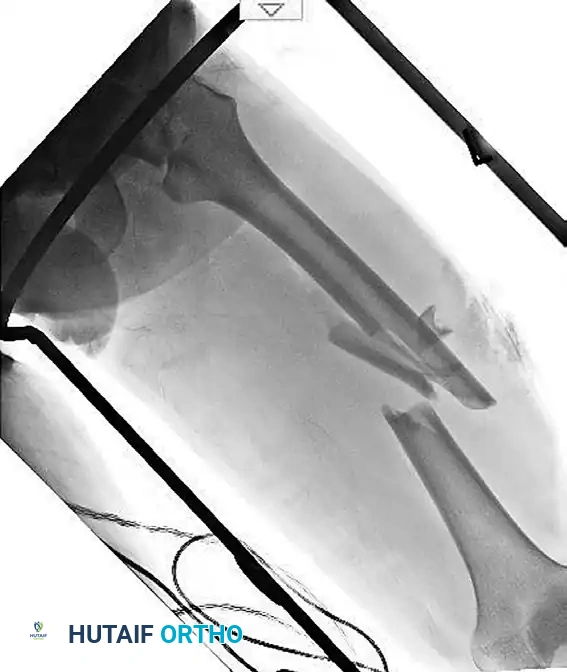

Figure 55-62A: Preoperative radiograph demonstrating a displaced ipsilateral femoral neck and shaft fracture.

Figure 55-63A: Preoperative radiograph of a femoral shaft fracture. The subtle nondisplaced femoral neck fracture was initially missed.